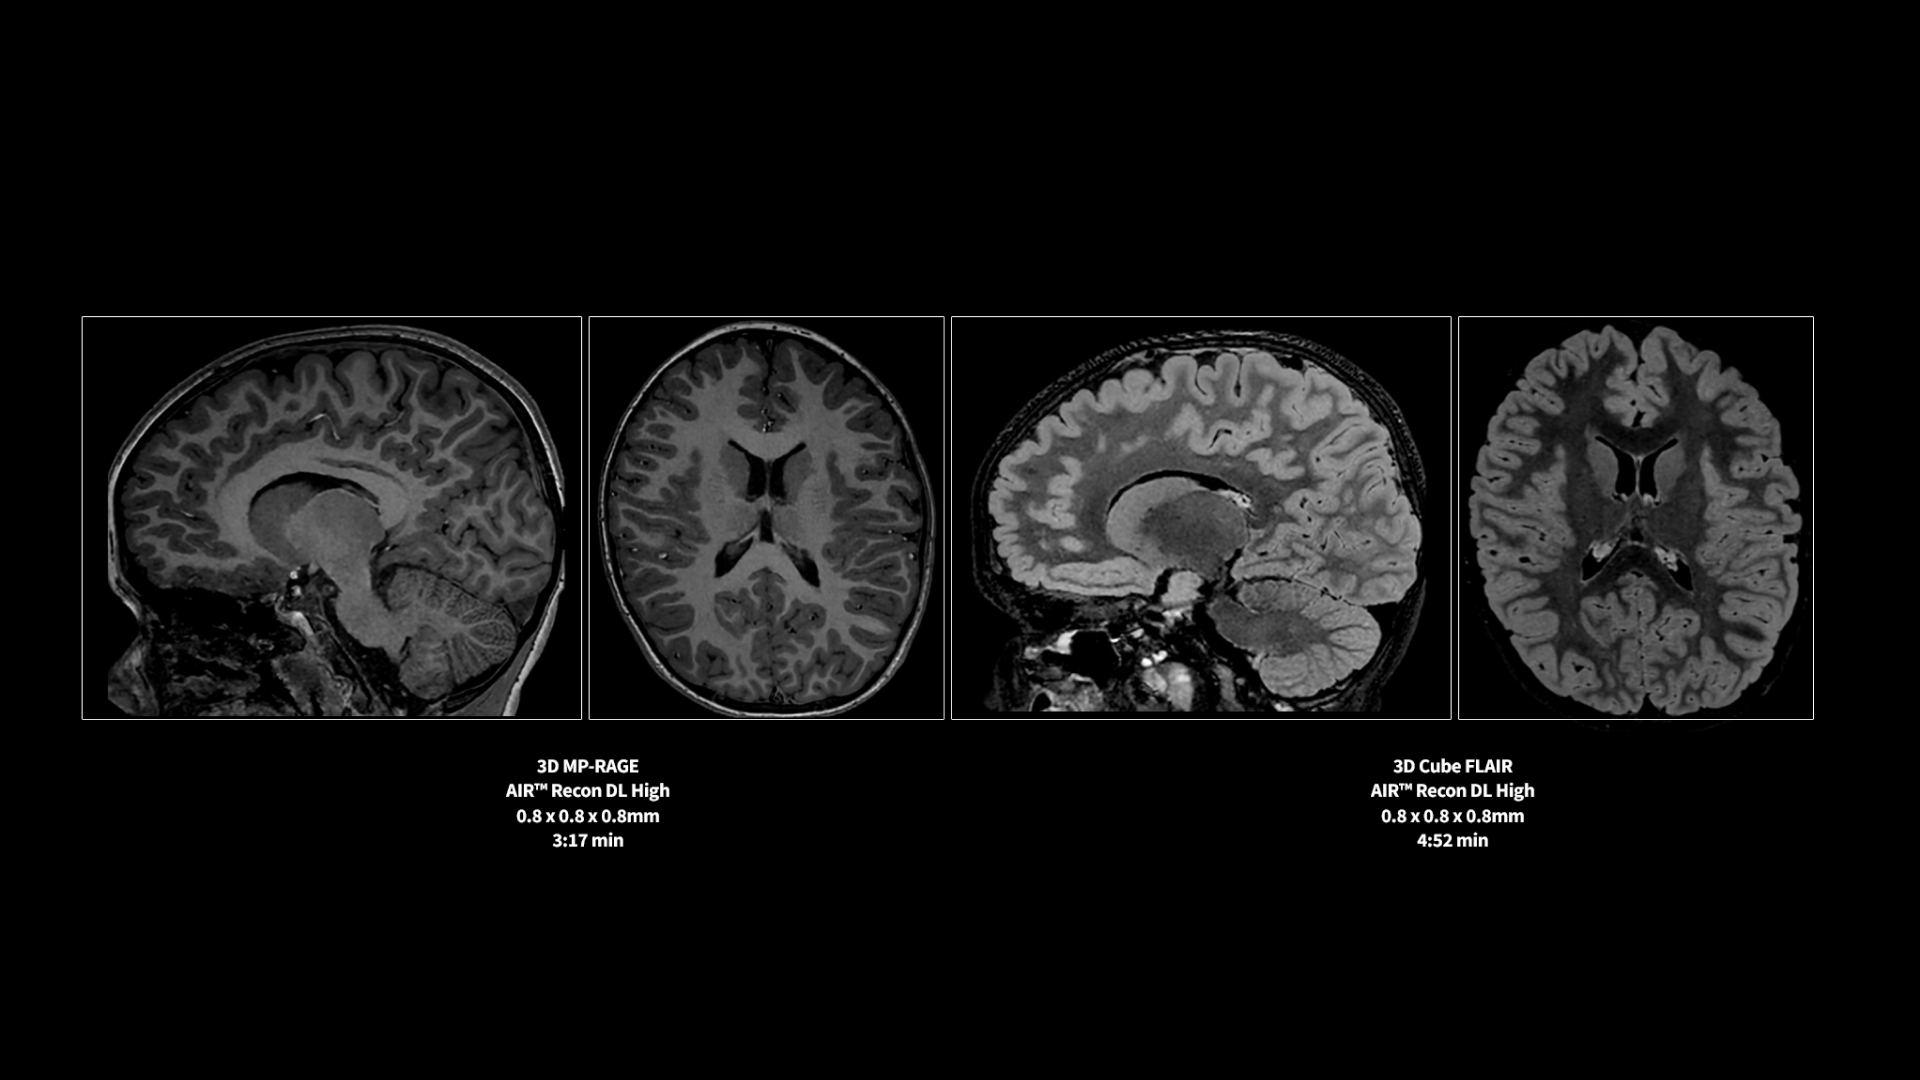

Pin-sharp image quality and exceptional speed with AIR™ Recon DL and Sonic™ DL​

SIGNA™ Premier offers the versatility you need to fulfill all your clinical needs. Explore the advanced imaging and clinical capabilities achievable with the SIGNA™ Premier system.

Experience pin-sharp precision and remarkable speed with a 3T SIGNA™ Premier MRI scanner, coupled with AIR™ Recon DL and Sonic™ DL.